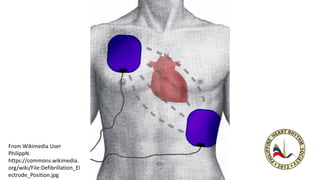

From Wikimedia User

PhilippN.

https://commons.wikimedia.

org/wiki/File:Defibrillation_El

ectrode_Position.jpg